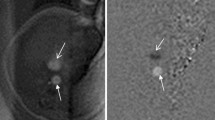

When possible, we chose SSFP sequences over T2-W sequences because of their superior umbilical vessel/eventration contrast. Volumetry was performed on a single plane, preferentially on transverse over sagittal orientation. We conducted the manual segmentation of eventrated organ volume, intraabdominal volume and total fetal volume using the open-source software application ITK-SNAP version 3.6.0 [20] (Fig. 2). Eventrated organ volume was identified and mapped first. To ascertain that umbilical vessels were not falsely labeled as eventrated intestine, we visually tracked the umbilical vessels from the placenta to the abdominal insertion. We determined the transition from eventrated organ volume to intraabdominal volume to be the plane where ventral abdominal muscle would have closed the abdominal cavity. Intraabdominal volume was mapped with the following anatomical borders. The superior boundary was formed by the thoracic cavity, respectively the diaphragm; delineation of intraabdominal organs from lung and heart was excellent, which in turn provided accurate mapping. The inferior border was defined at the height of the urinary bladder, which was not included in the intraabdominal volume; the kidneys were included in the intraabdominal volume. Anterior and lateral limits were the muscles of the abdominal wall. The posterior border was defined as the quadratus lumborum and psoas muscles as well as the spine, none of which was included in the intraabdominal volume. Figure 3 shows an example of the full volume in three dimensions. Full segmentation took approximately 100 min per subject on average. Segmentation of the intraabdominal and eventrated organ volume took about 20 min or less in most cases, while segmentation of total fetal volume took about 80 min.

Manual segmentation in a fetus at 22 weeks of gestational age. Transverse view is shown in this slice of a steady-state free precession sequence. Eventrated intestine is seen in blue. It is flanked by upper (✴) and lower (◆) extremities. The unmapped part anterior is the umbilical vessels. The feet are distal from the rest of the body (*). In the central lower part of the picture is the torso, with the abdominal cavity in yellow and abdominal wall muscle, spine, back muscle and diaphragm/lung in red. On the right side of the picture is the placenta, next to the fetus